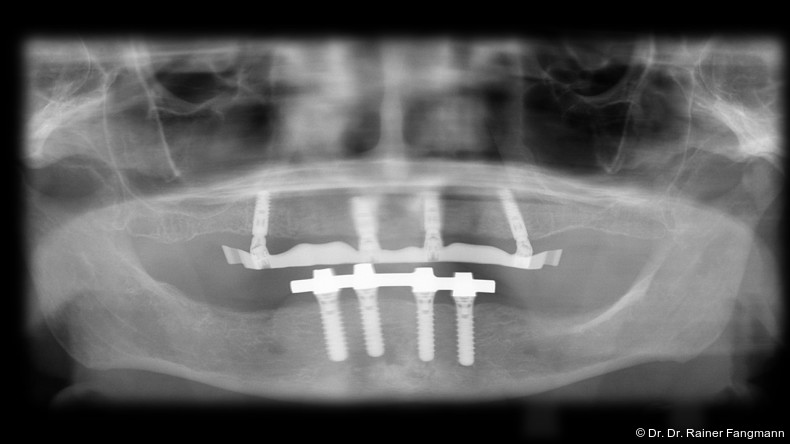

Die Fragestellung zur Implantatanzahl im Oberkiefer oder Unterkiefer ist oft sehr patienten- und behandlerspezifisch zu betrach-ten. Für Kostenträger ist die Frage oft von übergeordneter Relevanz. Für den Praktiker stellt sich die Frage nach der Umsetzbarkeit. Zudem sind auch das Knochenangebot und dessen Qualität für die Anzahl der Implantate und auch der Implantattypus maßgebend. Folgender Beitrag zeigt ein Fallbeispiel mit drei Implantaten, sechs Jahre in situ.

Ein immer viel diskutiertes Thema ist die Implantatanzahl beim All-on-X-Konzept. Diese ist von vielen Faktoren abhängig. Zu nennen sind der Implantattyp, der Implantatdurchmesser und die Implantatinnengeometrie. Im Weiteren sind die Knochenqualität und -quantität zu betrachten. Auch spielt die Gegenbezahnung zum All-on-X-Kiefer eine entscheidende Rolle, sodass hier keine einheitliche Linie für den Oberkiefer erkennbar ist. Es gelten in der Regel vier bis sechs Implantate als ausreichend. Im Unterkiefer sind es in der Regel vier. Wie dargestellt, reichen bei diesem Implantatsystem auch drei Implantate aus.